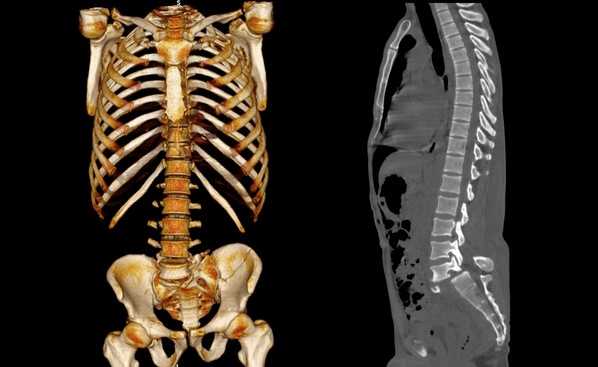

Трехмерная реконструкция при КТ

Сколиоз позвоночника на снимках КТ